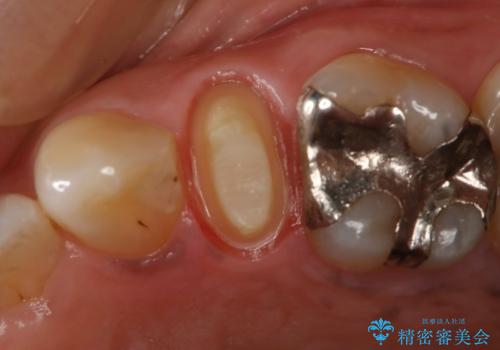

- 左上5番根尖部歯肉に膿ができ、治療を希望された患者様です。

神経が失活し根尖病変も見られるので、精密根管治療とクラウンでの治療を計画しました。

セラミックでの治療を希望されたので、フルジルコニアクラウンでの治療を選択しました。